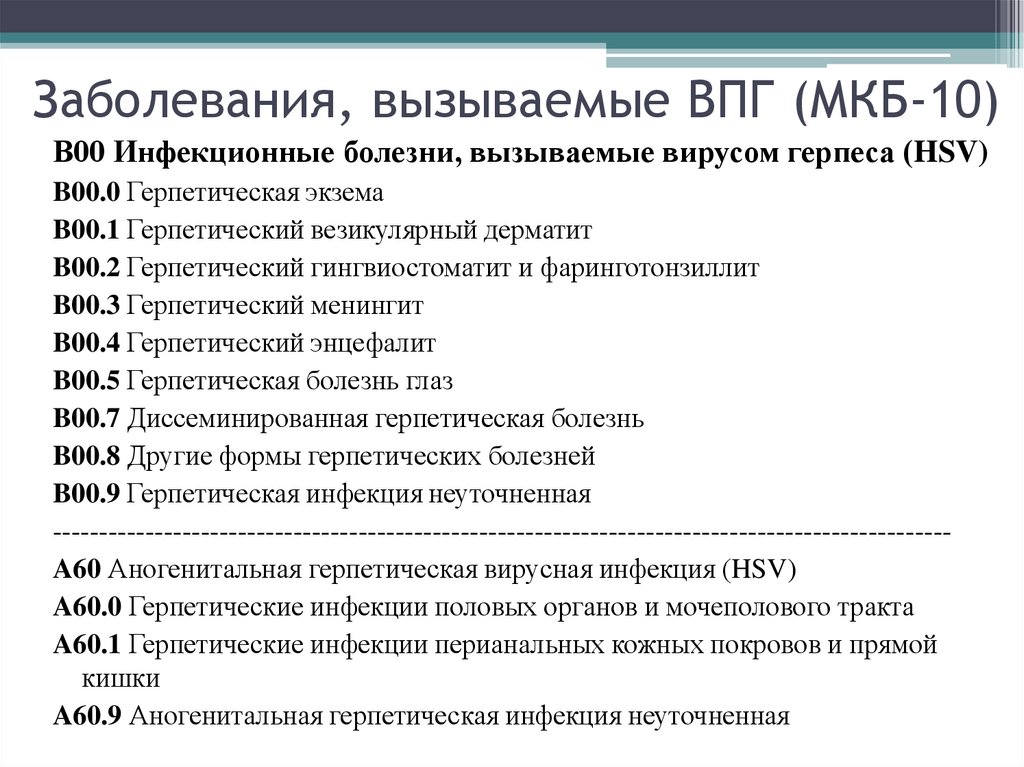

Код мкб 10 атерома головы

Код мкб 10 атерома головы 109 фото